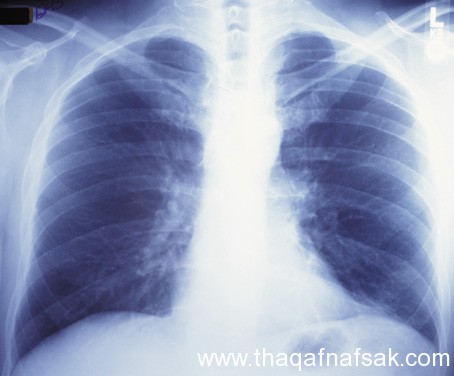

الاقلاع عن التدخين

تدخين حتى سيجارة واحدة في اليوم يزيد من فرصتك للإصابة بسرطان الرئة والمثانة والكلى والحلق والفم. الطريقة الوحيدة لخفض فرصها في الحصول على أي نوع من السرطان هو عن طريق إزالة التدخين من حياتك. التدخين السلبي هو أيضا خطير جدا لأنه يحتوي على ما يقرب من أكثر من 60% من الخلايا المسرطنة المعروفة. وبالتالي، الحد من التعرض للتدخين لمنع السرطان على المدتدابير السلامة من أشعة الشمس